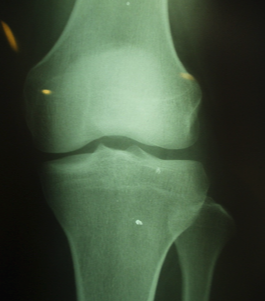

성장판 검사 방법은 많지만 가장 정확한 방법은 X-ray 촬영입니다.

X-ray로 성장판을 검사하면 손이나 골반, 무릎관절, 팔꿈치관절, 발목관절을 사용해서 골연령을 평가하는데요.

신체의 여러 뼈 중에 왼쪽 손목을 X-ray 촬영하는 것이 가장 정확한 검사 방법입니다.

손목뼈는 뼈조직이 만들어지는 순서가 일정하고 다른 부위의 사진과 비교해도 정확도가 떨어지지 않는데다가 촬영이 용이하기 때문이죠.

성장판 검사는 나이에 따라 검사 부위가 다른데 청소년의 경우 어깨를 같이 찍기도 하고, 1세 미만의 경우 무릎 사진을 같이 찍기도 합니다.